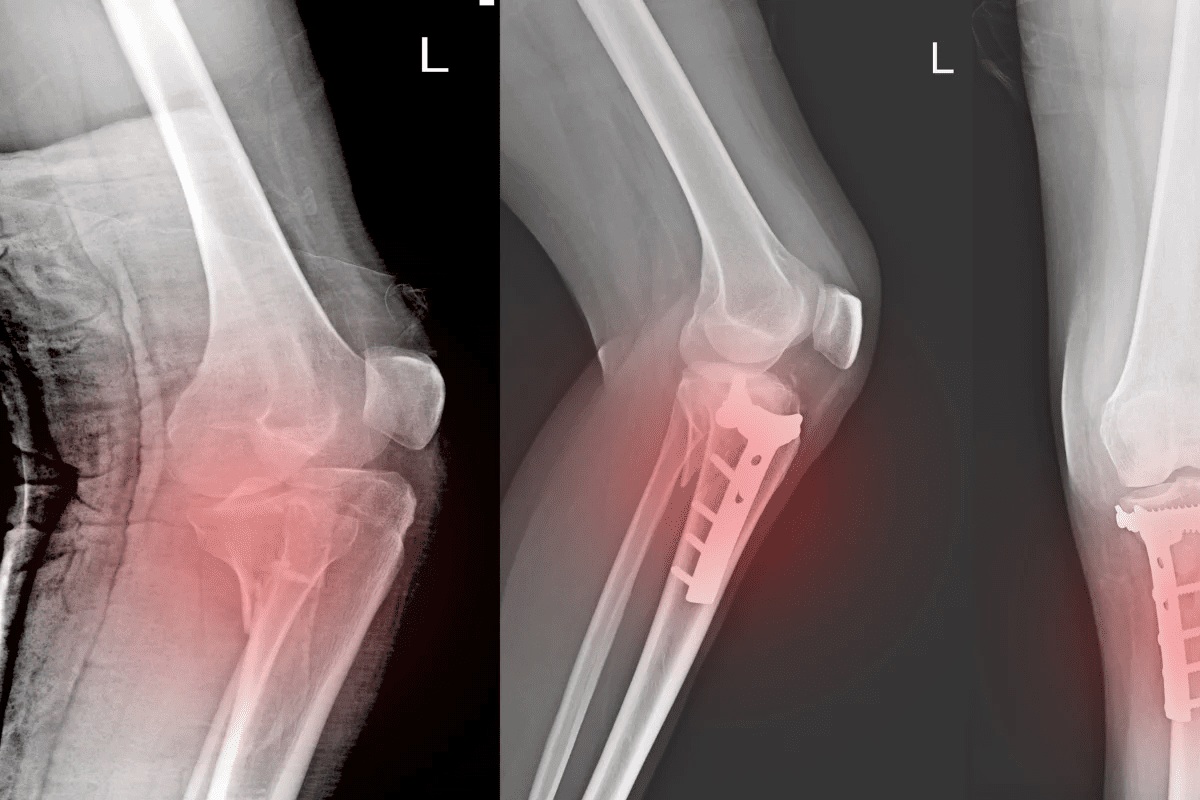

Surgical Stabilization: Plates, Screws, and Rods

For severe Tibia bone fractures or complex scaphoid bone fracture cases, internal fixation is often required.

• Plates and screws: To hold fragments of bone together near a joint.

• Intramedullary rods: High-strength metal rods placed inside the hollow center of long bones like the tibia.

• External fixation: A frame outside the body used to stabilize the bone when the soft tissue is too damaged for internal surgery.

These high-tech procedures provide immediate stability, often allowing the patient to begin moving the nearby joints much sooner than with a traditional cast.